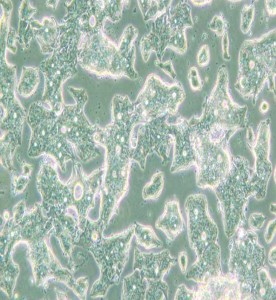

SW948人結(jié)腸腺癌細(xì)胞(DMEM)主圖

SW948人結(jié)腸腺癌細(xì)胞(DMEM)

中文名稱 : 人結(jié)腸腺癌細(xì)胞

細(xì)胞簡(jiǎn)稱 : SW 948

細(xì)胞形態(tài) : 上皮細(xì)胞樣